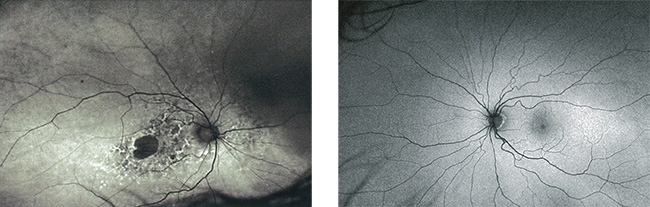

左:加齢黄斑の症例。

Optomap af 画像、地図状萎縮および病変と周辺部の間の自己蛍光パターンの異常を示している。

右:正常